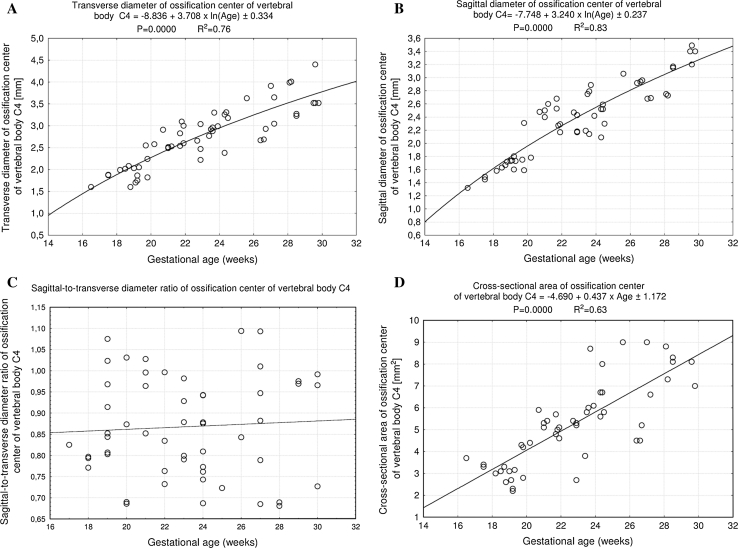

Fig. 5.

Regression lines for transverse diameter (a), sagittal diameter (b), sagittal-to-transverse diameter ratio (c), and cross-sectional area (d) of the ossification center of the vertebral body C4

The size of the ossification center of the C4 vertebral body has been presented in Table 3, while Fig. 4 presents the three ossification centers of vertebra C4 within its body (1), and right (2) and left (3) neural processes in fetuses aged 17, 22, 26, and 30 weeks, respectively. During the analyzed period, the transverse (Fig. 5a) and sagittal (Fig. 5b) diameters of the ossification center of the vertebral body grew logarithmically from 1.60 to 3.74 ± 0.44 mm, and from 1.32 to 3.37 ± 0.12 mm, according to the following models: y = − 8.836 + 3.708 × ln(Age) ± 0.334 (R 2 = 0.76) and y = − 7.748 + 3.240 × ln(Age) ± 0.237 (R 2 = 0.83), respectively. As a result, the growth dynamics for transverse and sagittal diameters decreased with gestational age, from 0.21 to 0.13 mm per week, and from 0.19 to 0.11 mm per week (P < 0.01), respectively. During the study period, the sagittal-to-transverse diameter ratio of the ossification center (Fig. 5c) increased from 0.86 ± 0.04 to 0.88 ± 0.11 (P < 0.05). The cross-sectional area of the ossification center (Fig. 5d) increased linearly from 3.70 mm2 in fetuses aged 17 weeks to 10.23 ± 3.14 mm2 in fetuses aged 30 weeks, according to the function: y = −4.690 + 0.437 × Age ± 1.172 (R 2 = 0.63). Similarly, the volumetric growth of the ossification center (Fig. 6a), from 4.67 to 13.45 ± 3.20 mm3, followed linearly as y = −5.917 + 0.582 × Age ± 1.157 (R 2 = 0.77).